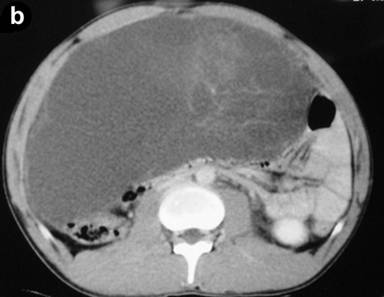

Clinical examination revealed abdominal swelling with generalized tenderness occupying the whole abdomen and almost reaching up to the pelvis. Blood investigation revealed polymorphonuclear leukocytosis (total leukocyte count 12,600 mm-3, reference range: 4,000-11,000 mm-3; polymorphs 91%, reference range: 40-75%). The serum amylase level was 297 U/L (reference range: 20-85 U/L). Liver function tests and CA 19-9 levels were normal. An ultrasound carried out outside our hospital found a large septate cystic collection in front of the pancreas and reported as acute pancreatitis with fluid collection. A CT scan revealed a large multiseptate cystic lesion (23.2x11.7x26.2 cm) anterior to the pancreas reaching up to the pelvis and displacing the gut loops behind and downwards (Figures 1 and 2). We decided to perform a laparotomy with a presumptive diagnosis of cystic neoplasm of the pancreas.

Figure 2. CECT sagittal (a.) and coronal (b.) scan of the abdomen. |